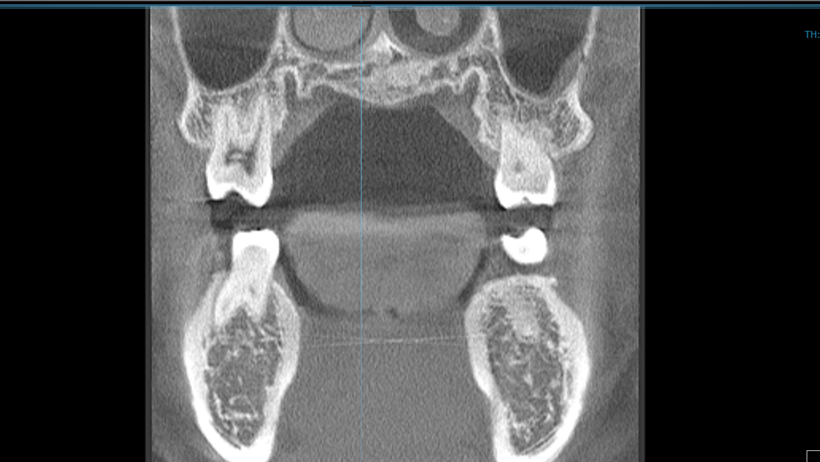

実際のCT撮影を行ったデータがこちらです。(頭部エックス線規格写真の時と同じく私です)

スライス画像をPC上で構築したものは、見たいところを見たい角度で確認することができます。2枚の写真は何を見ているのかというと、歯の顎の骨に入り込んでいる歯根(しこん)の位置を見ています。

歯は歯根を通じて顎の骨の中にあり、骨の厚みは年齢、性別、人種、また歯の場所によって異なります。インビザライン矯正治療で歯を動かしていく際に、効率的な移動の計画を立てたり、綺麗な歯並びだけでなく、長期安定を期待できる歯並びを確立するためにも、歯と骨の3次元的な位置関係を把握して治療計画を立てていきます。